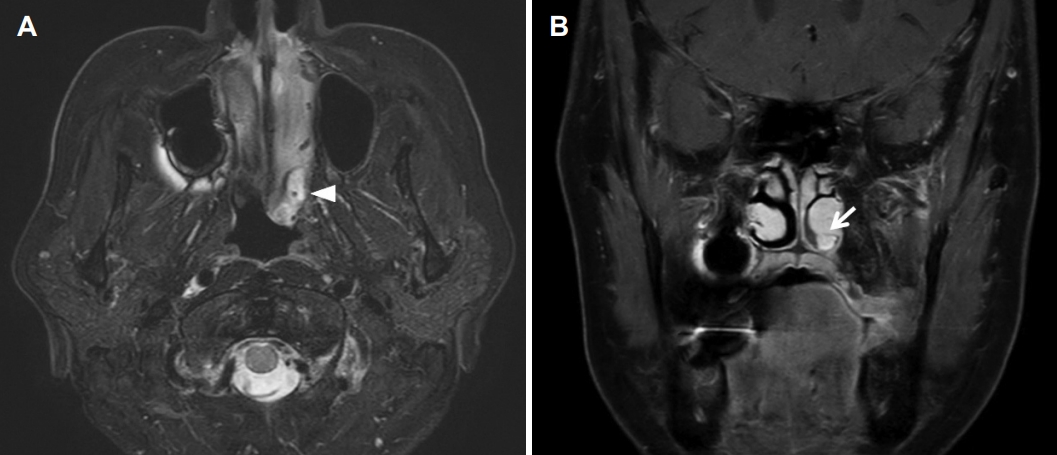

종물을 감별하기 위해 펀치 생검(punch biopsy), 부비동 전산화단층촬영(computed tomography, CT) 및 자기공명영상(magnetic resonance image, MRI)을 시행하였다. 펀치 생검의 결과는 다수의 급·만성 염증 세포가 존재하는 것으로 보고되었다. CT 영상에서 좌측 하비도의 점막비후가 관찰되었으며, 하비도 후방의 기저부에서 연조직 음영이 관찰되는 것 이외 주변의 골결손이나 양측 부비동 및 비강에 특이소견은 없었다(Fig. 2). MRI T2 조영 증강 영상에서는 좌측 하비갑개 후방에서 시작하여 후비공까지 차지하고 있는 종물이 강한 신호강도를 보였다(Fig. 3).

후비공 비용은 비내시경 검사에서 비강을 채우고 후비공까지 진행하는 비용 형태의 소견을 보이며, 영상의학적 검사는 비용의 기시부와 범위를 파악하고 감별 진단을 하는 데 도움이 된다. CT 영상에서 후비공 비용은 본 증례와 같이 비부비동에서 후비공까지 진행하는 저음영의 단일성 종물로 보이며[10], MRI 영상에서는 T1 강조영상에서 저신호강도, T2 강조영상에서 고신호강도 신호를 보여 악성 종양을 비롯한 비강에서 발생할 수 있는 단일성 질환의 감별에 도움이 된다[2]. 후비공 비용이 하비갑개에서 발생하는 경우는 매우 드물기 때문에 감별 진단으로 반드시 반전성 유두종(inverted papilloma)을 고려해야 하며[4,6], 그 외에도 비부비동염에 동반된 비용, 점액낭종(mucocele), 혈관섬유종(angiofibroma), 혈관종(hemangioma) 등 편측성 비부비동 내에서 종양으로 나타날 수 있는 질환들을 감별해야 한다[2,6]. 본 증례는 비내시경 및 영상검사에서 좌측 하비도의 후방에서 후비공까지 진행되는 종물이 확인되었지만, 종물의 경계가 지저분하고 종물의 발생 지점이 일반적이지 않아 처음에 후비공 비용을 고려하지 못하였다.

Fig. 1.Preoperative endoscopic findings. A bizarre single polypoid mass (*) is located between the left inferior turbinate and the basal floor of the nasal cavity. S: septum, IT: inferior turbinate. Fig. 2. Preoperative CT findings. Axial (A) and coronal (B) view. CT shows soft tissue density at the basal floor of the nasal cavity. Bone erosion is not observed and paranasal sinus is clear. Fig. 3.Preoperative MRI findings. Axial (A) and coronal (B) view. An ovoid homogenous enhancing mass (arrowhead) appears to originate from the posterior inferior side of the left inferior turbinate (arrow) and extends to the choana. Fig. 4. Operative findings. A pedicle (arrow) of single polypoid mass (*) is attached to the posterior side of the inferior turbinate. REFERENCES1. Lopatin A, Bykova V, Piskunov G. Choanal polyps: One entity, one surgical approach? Rhinology 1997;35(2):79-83.